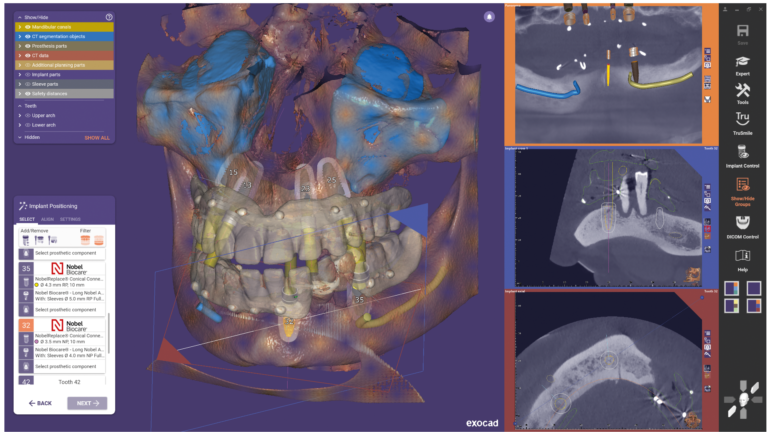

Blijdent BV is an authorized dealer of Medit lab scanners, Medit intra-oral scanners, iTero intra-oral scanners, Exocad design software, Exocad training courses, Nextdent 3D printers, Formlabs 3D printers, and Roland milling machines with Millbox CAM software. Recently, the ModJaw system also became available through Dentalhouse.

Dentalhouse develops its own digital workflows, for example for digital prostheses, based on Exocad software. Dentalhouse has its own helpdesk for support via telephone, team viewer, etc.